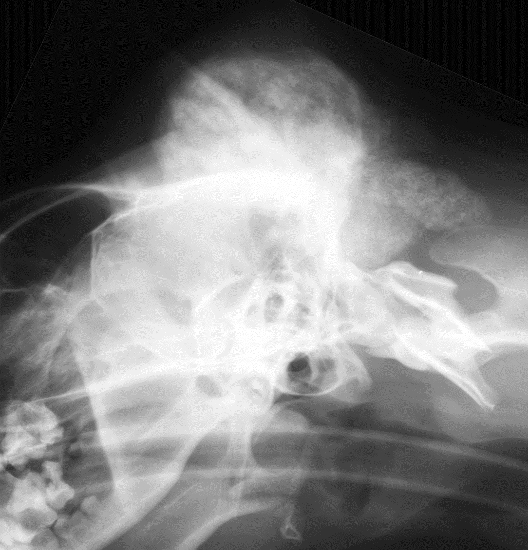

What is shown in this image?

craniomandibular osteopathy

What is shown in these images?

craniomandibular osteopathy -bone proliferation caudal and lateral to TMJs, but not ON the TMJ joints themselves